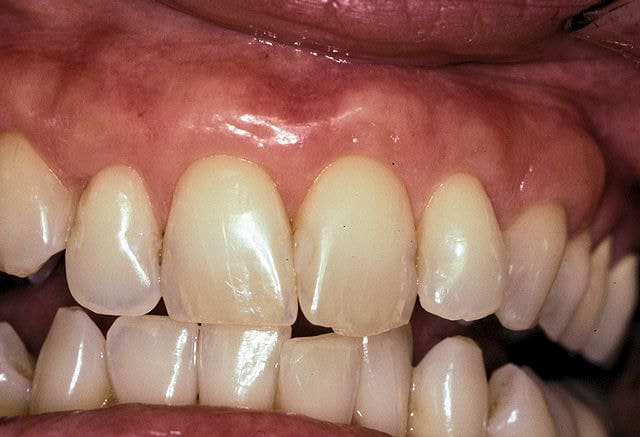

After

Before